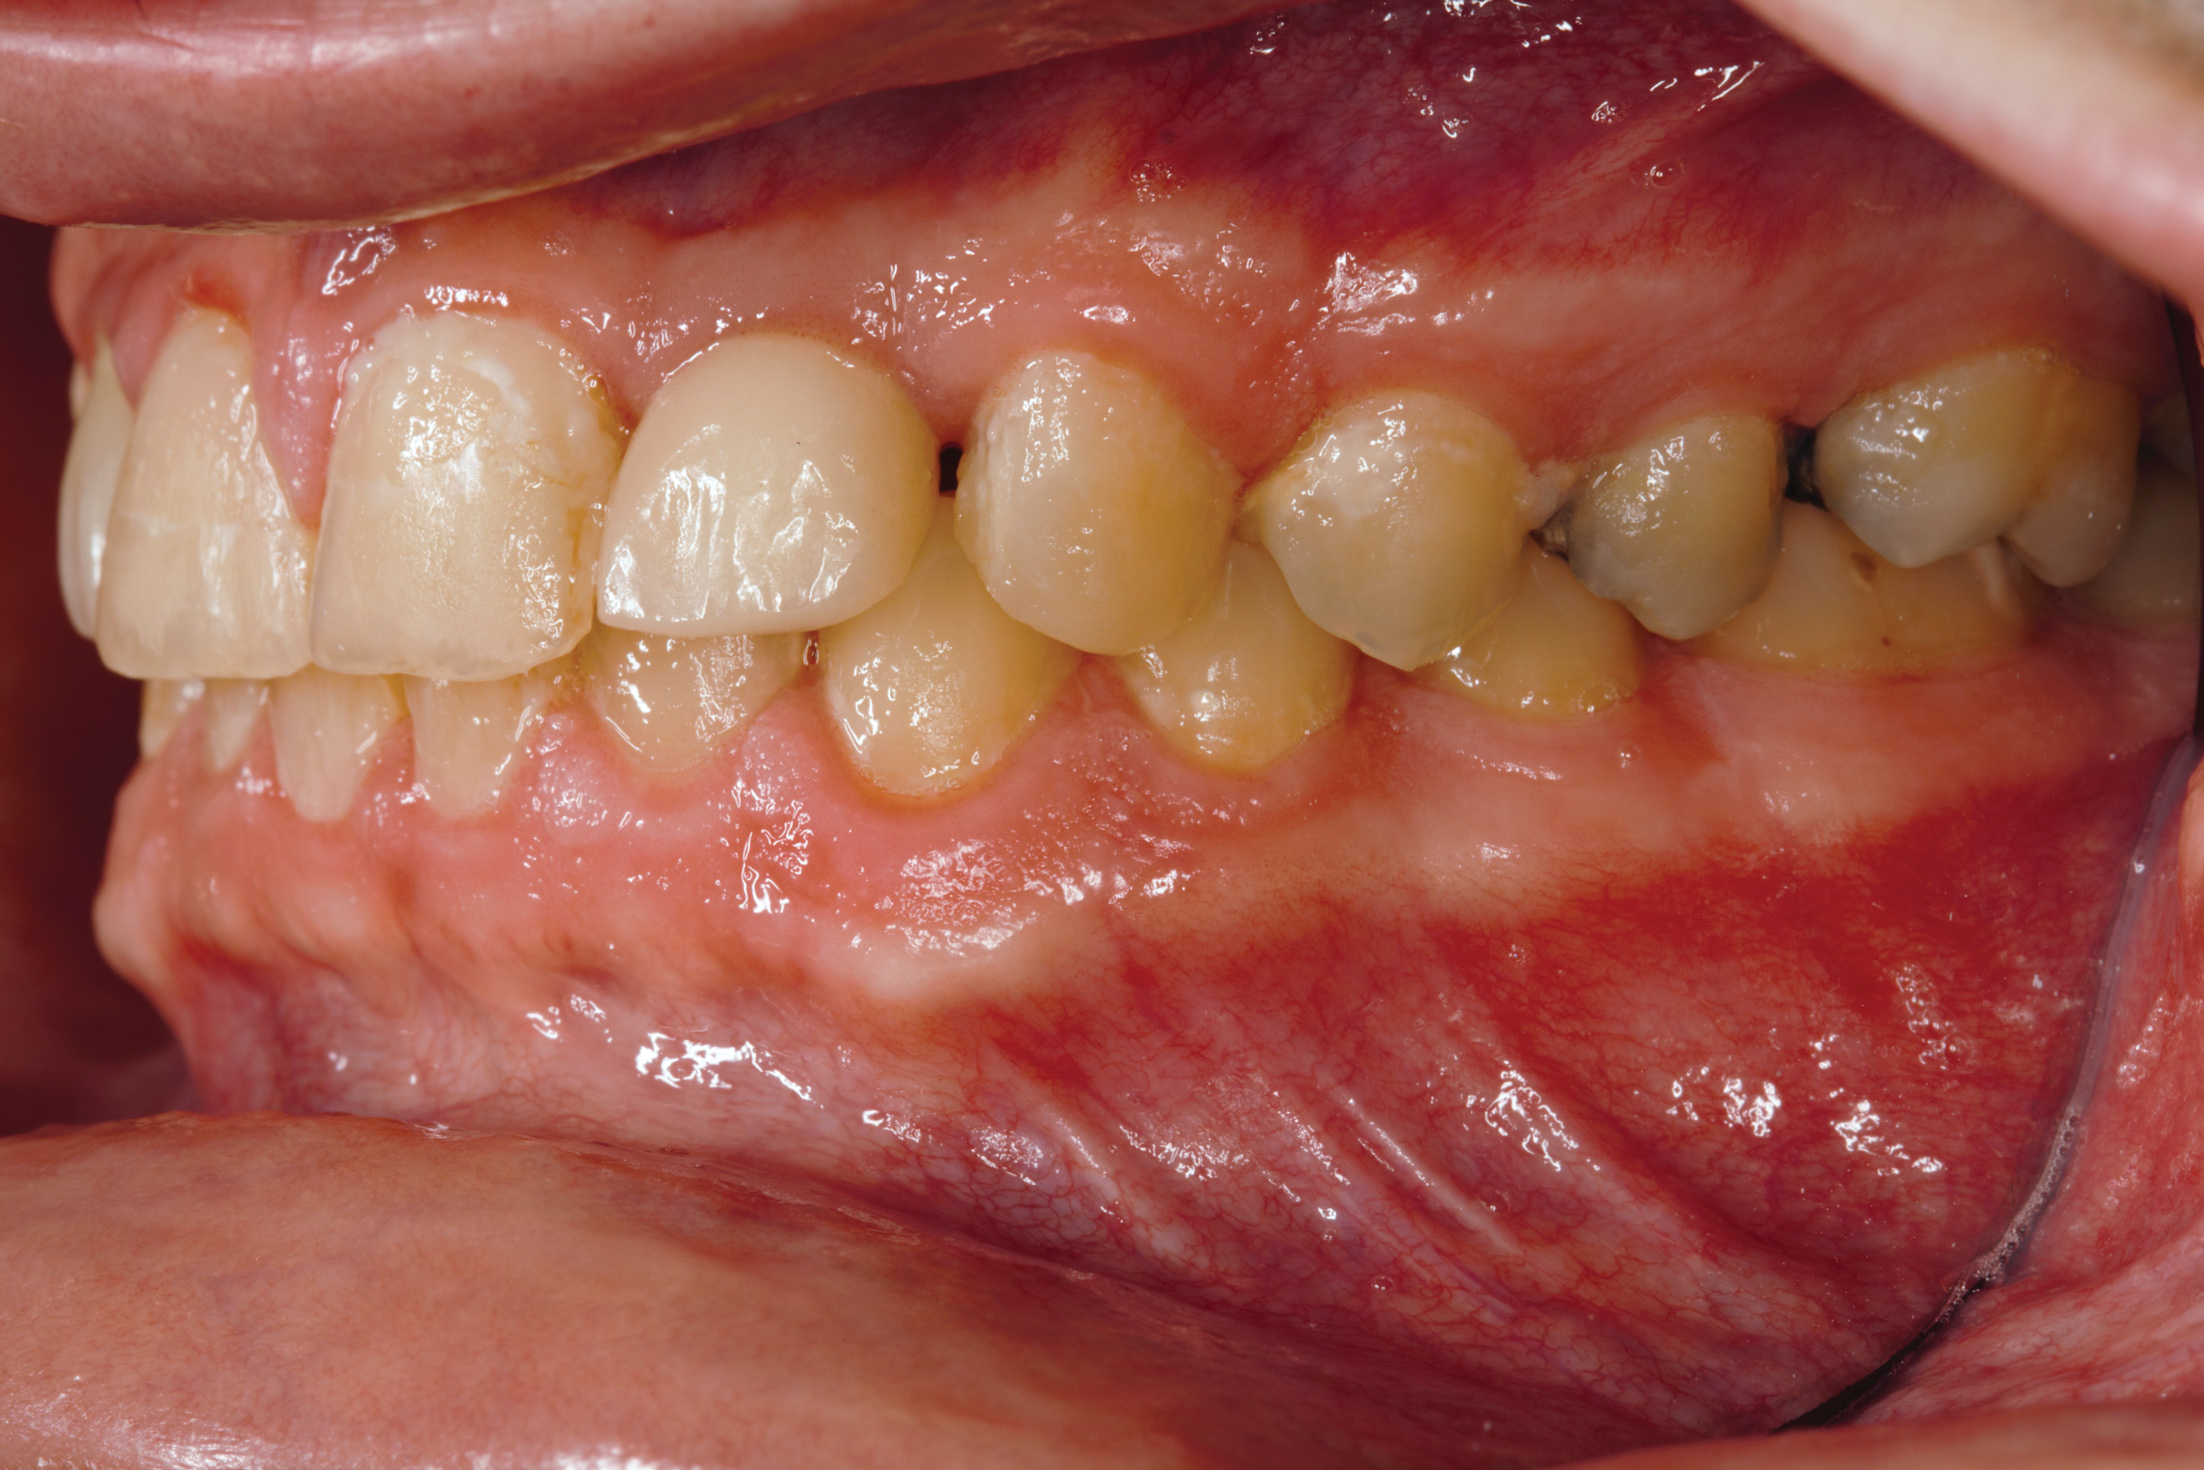

Fig 14.  Prosthetic phase completion. Left lateral view. Note vertical dimension change in posterior as evidenced by the buccal cusp tip position of tooth No. 12 versus papillary tissue of teeth Nos. 20 and 21 as compared to initial presentation (Fig 4).

Figure 14